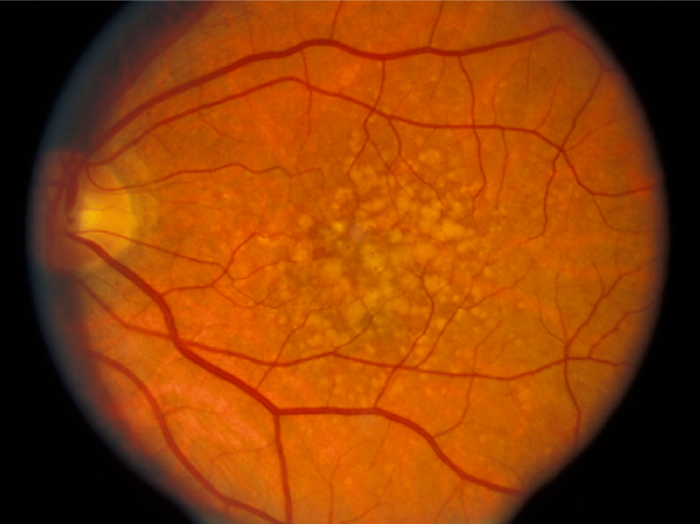

A Targeted Inhibitor Of The Alternative Complement Pathway Accelerates Recovery From Smoke-Induced Ocular Injury

Inhibition Of The Alternative pathway Of Complement Accelerates Recovery From Smoke-Induced Functional And Morphological Ocular Injury

The Alternative Complement Pathway Deficiency Amerliorates Chronic Smoked-Induced Functional And Morphological Ocular Injury

Retinal Metabolic Response to Cigarette Smoke

The Alternative Complement Pathway Mediates Functional And Morphological Deficits In A Smoke Model Of Age-Related Macular Degeneration

Retinal Metabolic Response to Cigarette Smoke